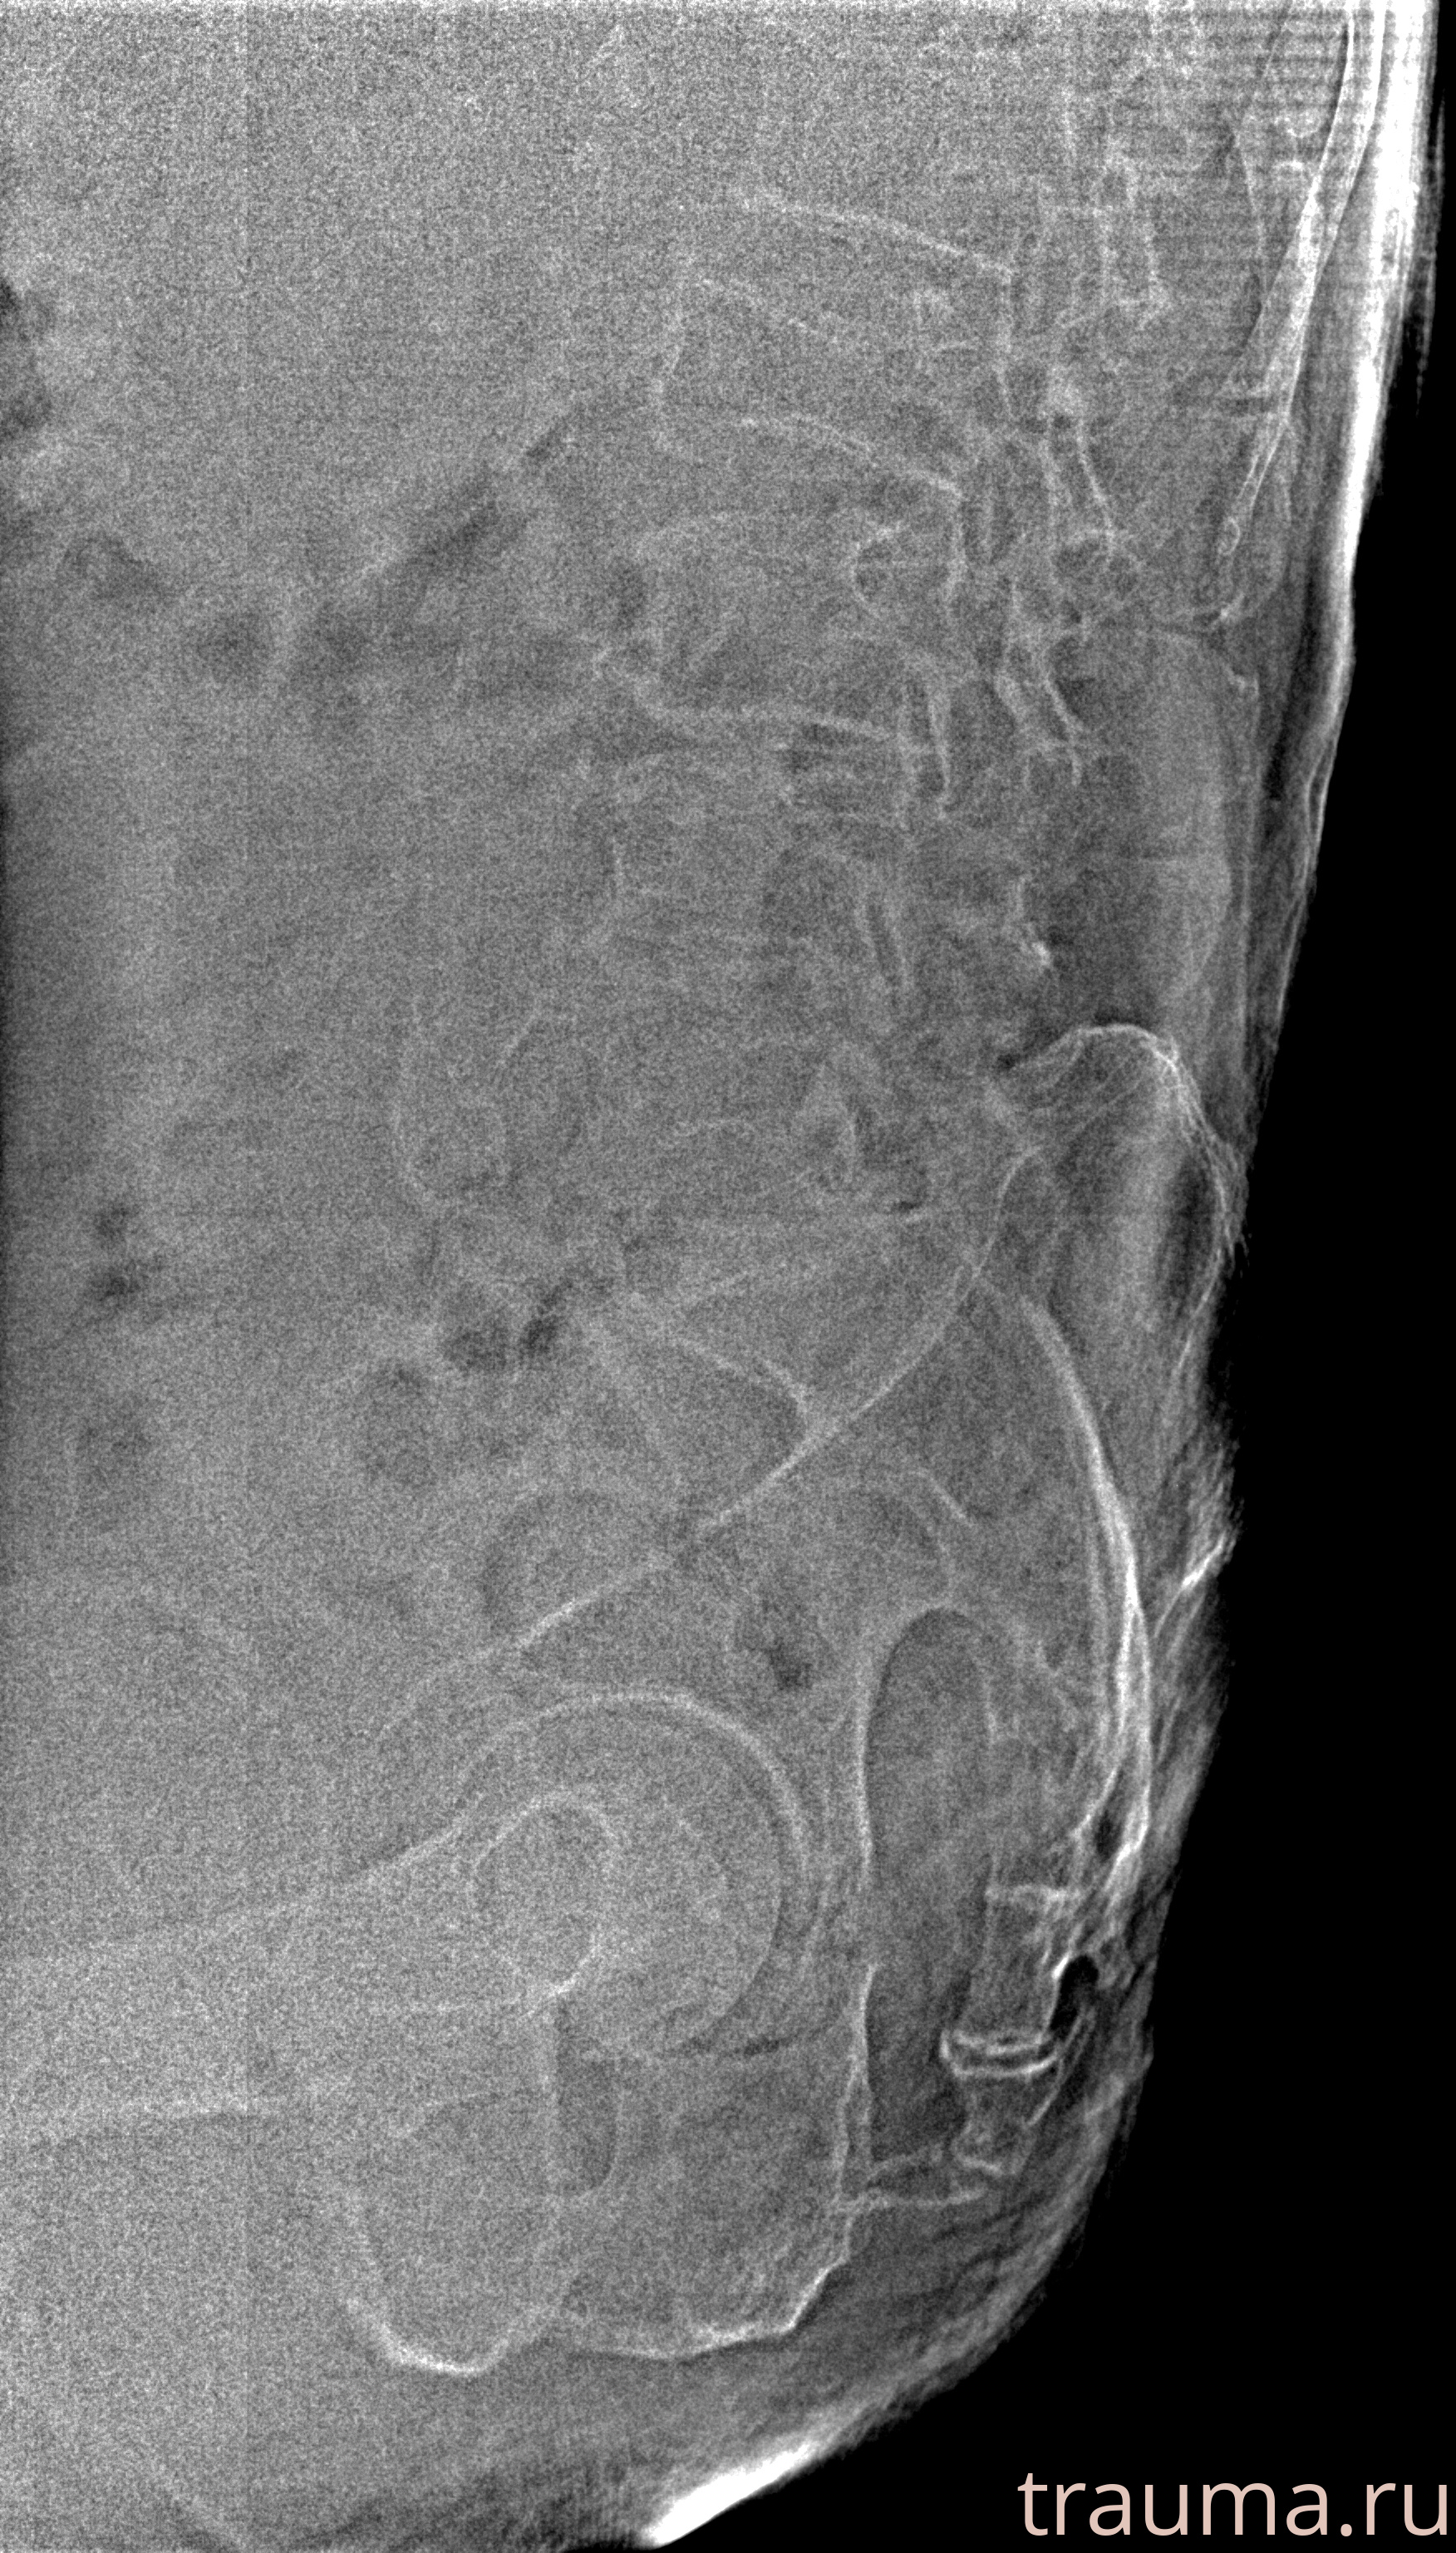

Рентгенограммы

Рентген на дому: по вашему адресу приезжает врач-рентгенолог, травматолог-ортопед с мобильным рентгеновским аппаратом, проводит диагностику травмы или заболевания, делает необходимые рентгенограммы, дает рекомендации по дальнейшему лечению. Получить качественные снимки в домашних условиях возможно благодаря уникальной методике, разработанной МосРентген Центром для института  Склифосовского